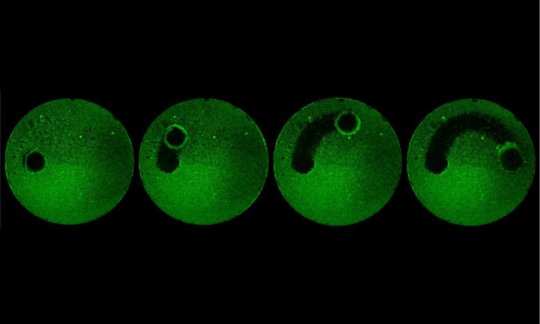

Together, the cross-school team designed, optimized, and tested two types of robotic systems, which the group calls catalytic antimicrobial robots, or CARs, capable of degrading and removing biofilms. The first involves suspending iron-oxide nanoparticles in a solution, which can then be directed by magnets to remove biofilms on a surface in a plow-like manner. The second platform entails embedding the nanoparticles into gel molds in three-dimensional shapes. These were used to target and destroy biofilms clogging enclosed tubes.

Both types of CARs effectively killed bacteria, broke down the matrix that surrounds them, and removed the debris with high precision. After testing the robots on biofilms growing on either a flat glass surface or enclosed glass tubes, the researchers tried out a more clinically relevant application: Removing biofilm from hard-to-reach parts of a human tooth.

The CARs were able to degrade and remove bacterial biofilms not just from a tooth surface but from one of the most difficult-to-access parts of a tooth, the isthmus, a narrow corridor between root canals where biofilms commonly grow.

“Existing treatments for biofilms are ineffective because they are incapabale of simultaneously degrading the protective matrix, killing the embedded bacteria, and physically removing the biodegraded products,” says Koo. “These robots can do all three at once very effectively, leaving no trace of biofilm whatsoever.”